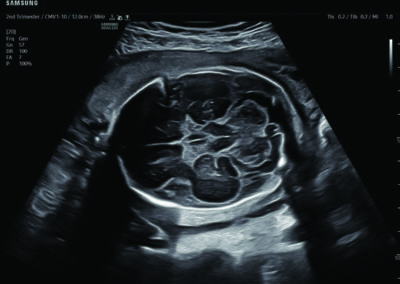

Procedural Services

Comprehensive, advanced and expert MFM care for high-risk pregnancies

- Neural tube defects

- Fetal anomalies